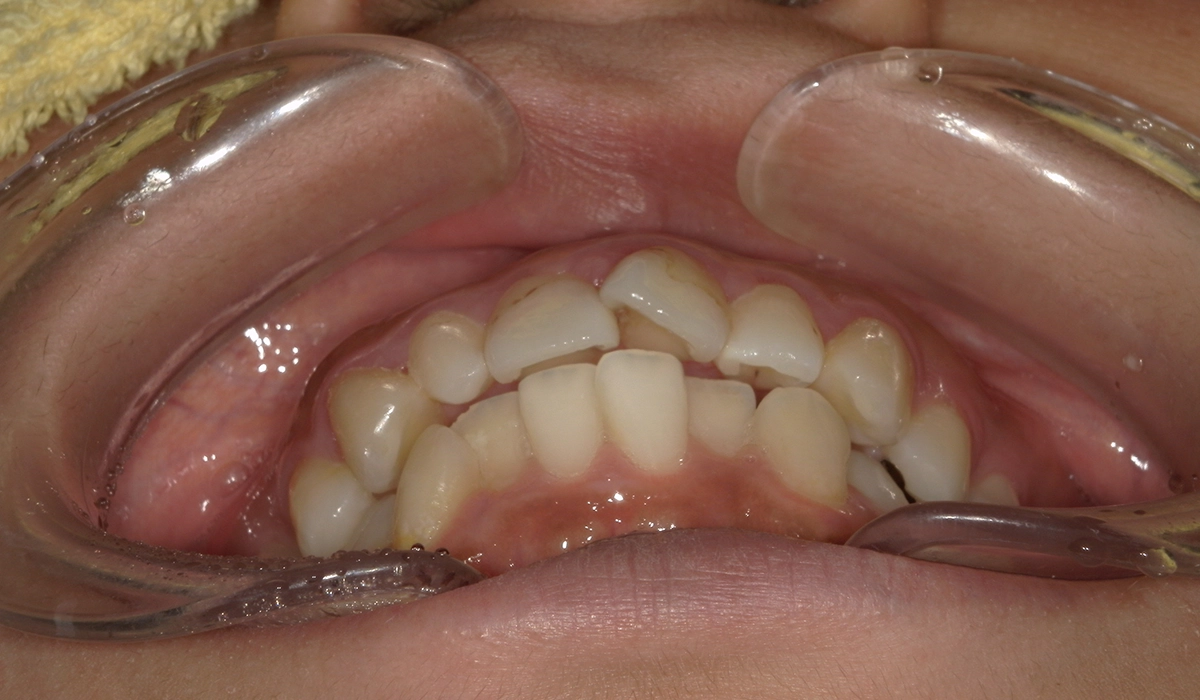

術前:右側

術後:右側